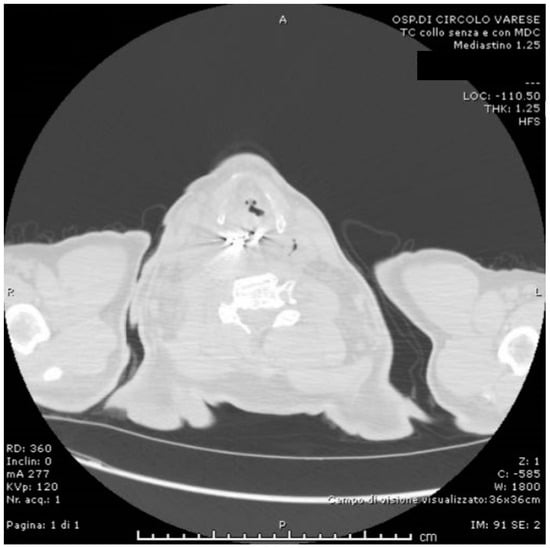

2. Case Presentation